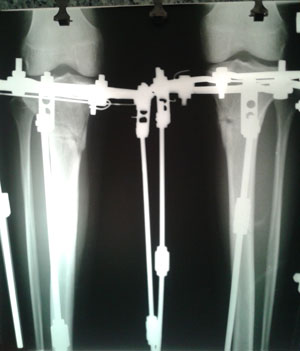

Рентген перед снятием аппаратов.

Вложения

20150107_115900.jpg

20150107_120009.jpg

Дата операции 25.08.2014г.

Дата снятия аппаратов 07.01.2015г.

Срок лечения 132 дня.